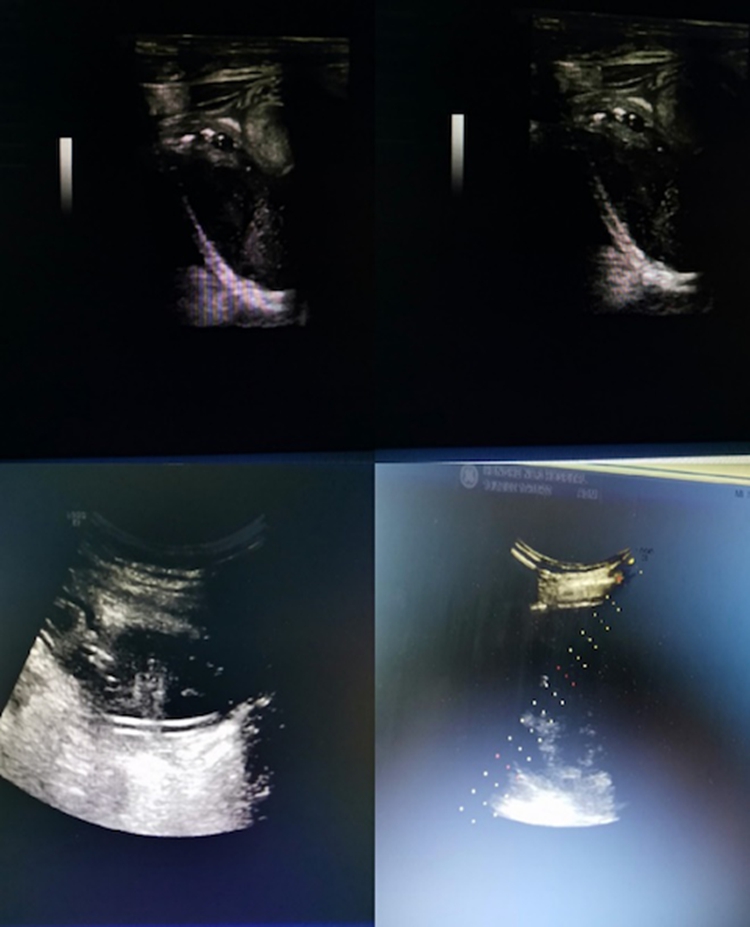

2019.12红河州三医院超声影像科:把边疆人民需要作为开展新技术新项目动力

超声引导下穿刺活检术

超声引导下经皮胆管穿刺置管引流术

超声影像科

超声造影技术

腹部脓肿穿刺抽吸和置管引流术